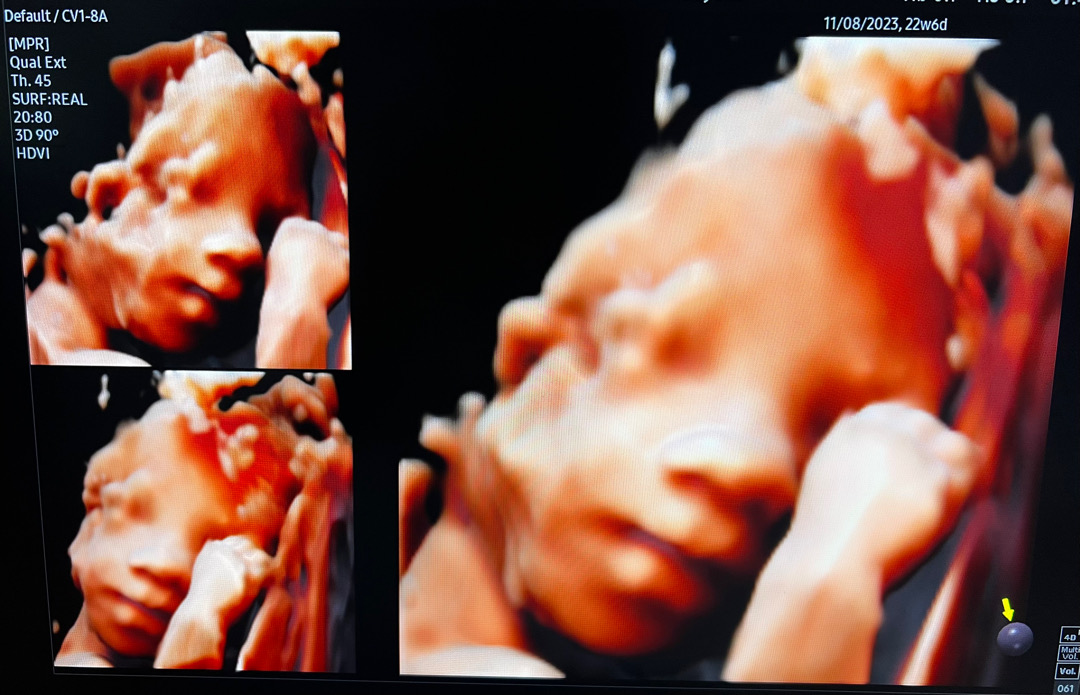

처음 찍어본 입체 초음파!

과연 실제로 만나면 제 유전자가 조금이라도 보일지 궁금해지는?! 남편 빼박 아들 사진 남기고 갑니다ㅎㅎ 달달한 주스 엄청 마시고서야 살짝 움직여줘서 그나마 촬영 성공했는데, 왼쪽 상단 사진에 살짝 웃어줘서 초음파선생님이 정말 뿌듯해하셨어요 🥰